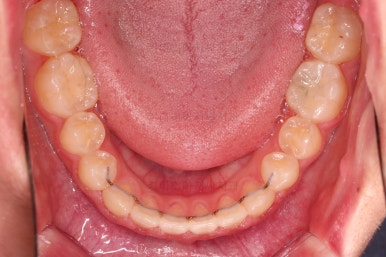

안정성을 충분히 확인한 뒤 치료를 종료합니다.

틈새가 벌어지더라도 뒤쪽에 벌어지라고 앞니쪽은 유지철사를 부착하고요.

동래교정치과 키다리아저씨치과만의 독특한 디자인의 유지장치를 추가로 드리게 됩니다.

악궁확장을 통해 위아래 악궁의 크기 조화를 맞췄고, 틈새도 모았으며 교합도 적절히 마무리를 했습니다.